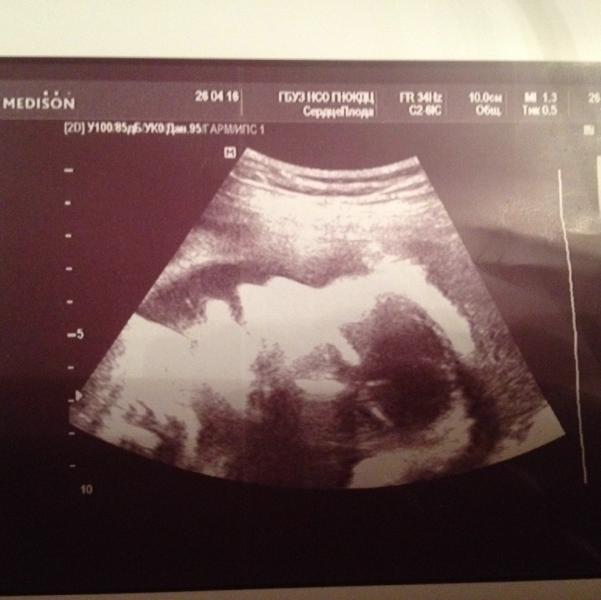

Бывает все таки приветливая бесплатная медицина! Была сегодня в одц на узи (эхо кг) сердца плода, специалист хоть и молодая, но очень понравилась! Изворачивалась и подлазила как могла, каждое действие комментировала, говорила что смотрит, измеряет, зачем, почему, в целом рассказала про пороки и что можно уже исключить, а что можно обнаружить только после рождения. С малышом разговаривала, улыбалась, умилялась ))) я вышла безумно довольная и с отличным эмоциональном подъеме! Ещё и фотографии дала мне , да не сердца, а личика нашего с носом -пуговкой и губками-уточкой.